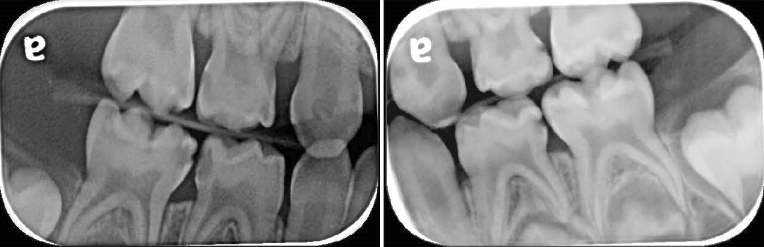

The patient was followed up three, six and ninth months later. He, nor his parents, had any complaints whatsoever. There were no issues with the occlusion, symptoms or signs of pulpal pathosis or sepsis affecting the molars. The bite had completely recovered. See Figures 4 (a, b, c, d & e). The parents’ satisfaction in reaching a positive outcome, without resorting to the use of GA, was very high. Post op radiographs (Figures 5 a & b) showed satisfactory clown placement and no recurrent caries.

Managing the upper anterior cavities with permanent restorations would have been impossible in this case due to the child’s lack of cooperation. Therefore, temporization of open cavities with GIC was a straightforward way to introduce the child to dental procedures. It was also advantageous in terms of preventing the progression of caries, reducing the chance of sepsis and pain, reducing the oral load of plaque and a good source for fluoride. Composite strip crowns will be considered as an alternative if cooperation allowed. Coincidently the patient’s 51 became discoloured, albeit asymptomatic. Although no history of trauma was elicited in this case, it was assumed to be the case. Persistent dark discolouration in the patient’s 51 may be associated with pulp necrosis. Since the tooth is asymptomatic clinically and in the absence of radiographic pathological signs (Figure 5 c), it was decided to keep under close review. Parents were aware that this tooth may require future treatment; a pulpectomy or extraction.